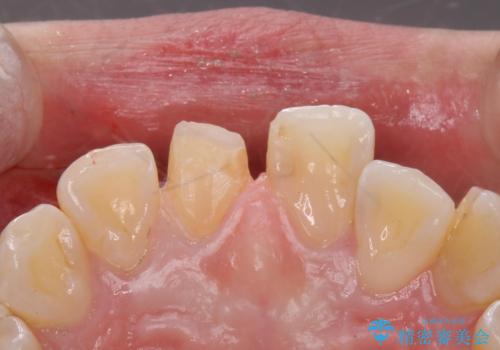

- 前歯のかぶせ物の色が気になるとのことで来院された患者様です。

セラミッククラウンで作り変えていきます。